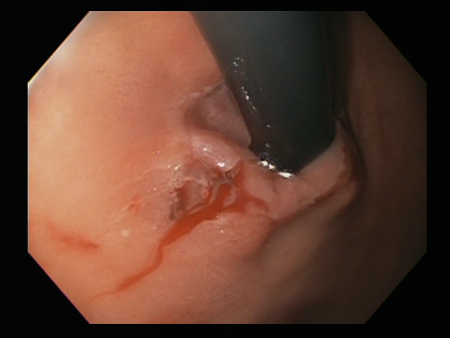

Bleeding Mallory Weiss Tear viewed on retroflexion

From the personal collection of Douglas Adler; used with permission